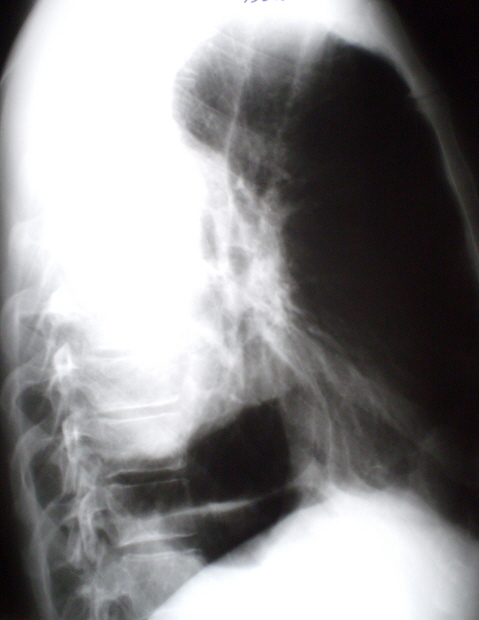

Иллюстрация 2. Рентгенограмма в левой боковой проекции. Верхняя доля левого лёгкого – компенсаторная эмфизема. Язычковый сегмент сниженной прозрачности с линейными «тяжеподобными» структурами. В задних отделах грудной клетки слева паракостально определяется значительных размеров снижение прозрачности легочной ткани в виде неправильной формы овальной тени, «широко прилежащее» к грудной стенке сзади и латерально. Данная фокусная тень значительной интенсивности, однородной структуры с неровным, но довольно четким контуром. С грудной стенкой данная фокусная тень образует «тупые углы».